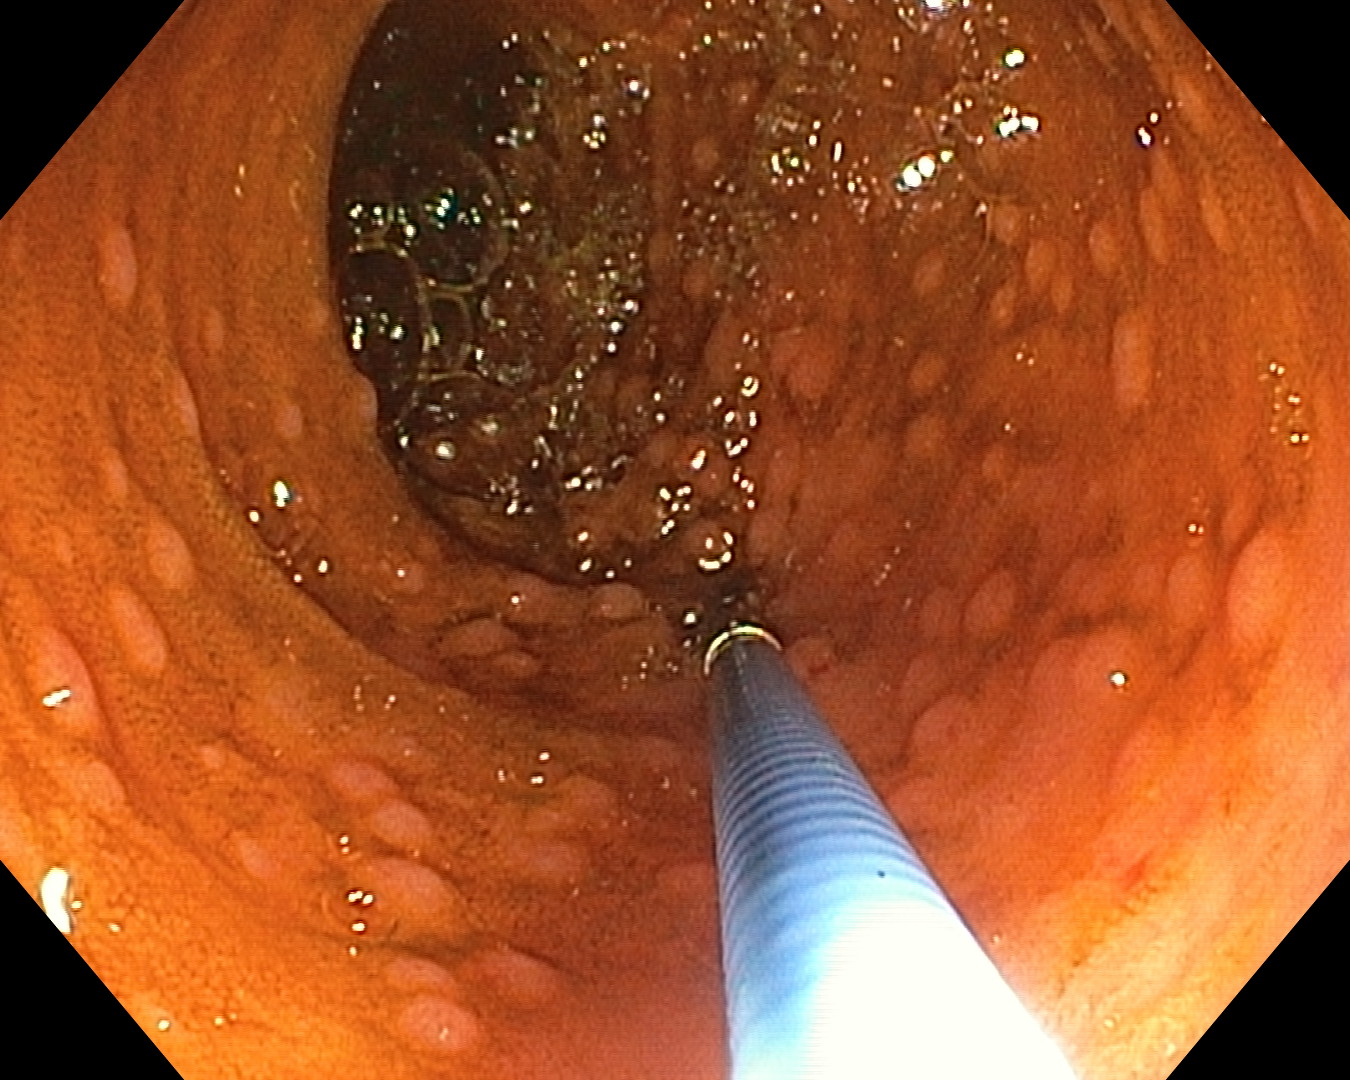

„Aparatul este prevăzut cu o spirală dintr-un plastic dur ce poate fi controlată electric cu ajutorul a două pedale, pentru înaintare și pentru retragere, totul realizându-se cu sprijinul unui motoraș atașat dispozitivului. Toate acestea sunt conectate la o unitate centrală. Mai mult, un controler permite oprirea automată a sistemului atunci când crește rezistența la înaintare sau la retragere. Trebuie spus că enteroscopia este examenul endoscopic gold standard pentru diagnosticul, dar și pentru tratamentul afecțiunilor la nivelul intestinului subțire.

Mai mult, aparatul pe care îl folosim permite recoltarea de biopsii, obținerea, practic, a unui fragment bioptic, ce este apoi analizat de histopatologi. În plus, se pot efectua diferite tehnici intervenționale. De exemplu, oprirea unei hemoragii prin aplicarea de hemoclipsuri, coagularea cu argon plasmă sau excizia de polipi”, explică conf. dr. Christian Banciu, șeful Secției Medicină Internă a Spitalului Clinic CF Timișoara.